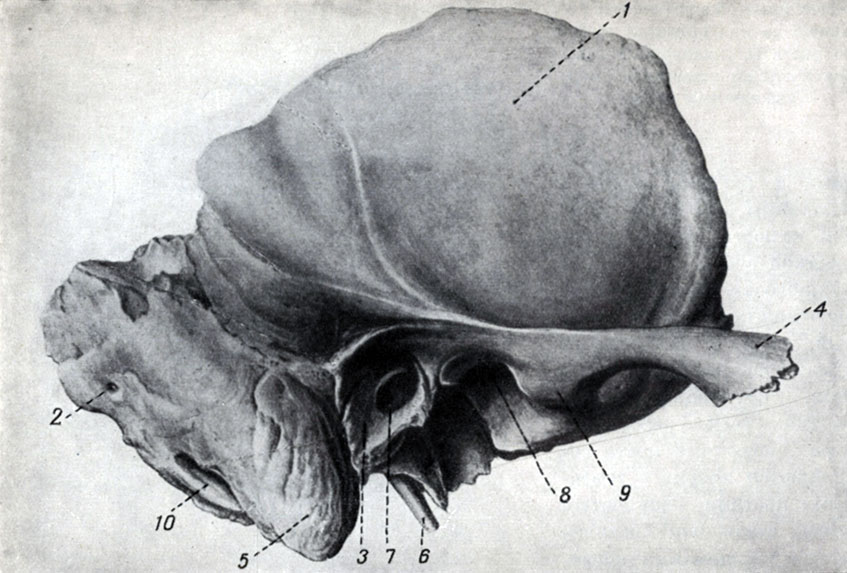

Анатомия и особенности фиссуры петротимпаника